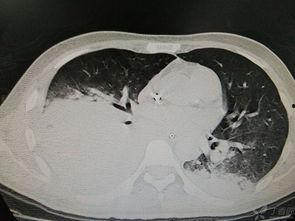

1. 身体状况:如果你有严重的肺部疾病,如肺炎、肺结核等,请在医生指导下进行。